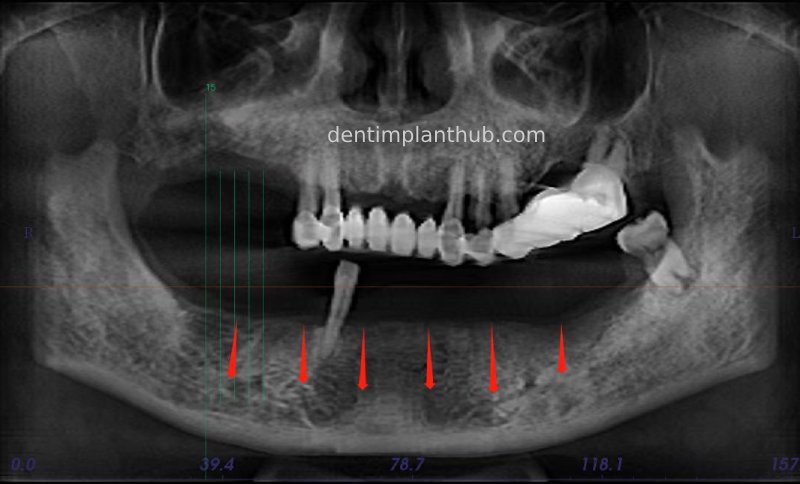

Pre-operative X-ray panorama on 8/2/23.

Details of surgery on 8 Feb 23.

All stumps were removed, rinsed with hydrogen peroxide and implanted with bone powder for site preservation, using 0.5 g of bone powder and a 1.5*2 periosteum.